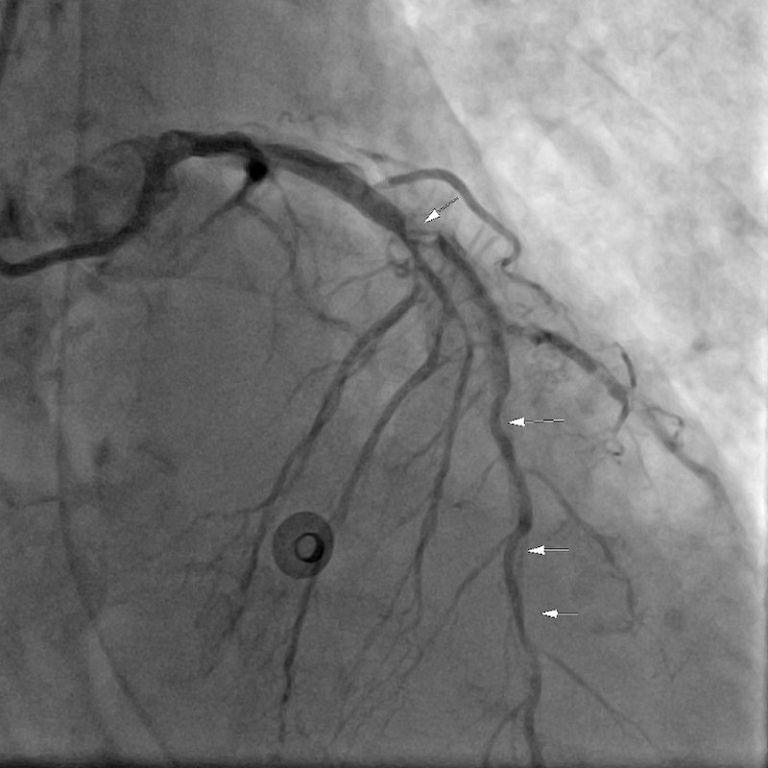

徐展陽醫師解釋,醫師可利用Impella其微小、軸型的特性,在複合式手術室透過X光以及經食道超音波導引之下,直接穿過主動脈瓣,深入左心室進行血液抽吸減壓,再由馬達遠端灌流入升主動脈直至全身;而傳統葉克膜系統是經由鼠蹊部逆向灌流,若病人心臟功能非常差,會與心臟原有血流對抗產生阻力,很可能造成心臟腫大、嚴重肺水腫、產生泡沫血痰、下肢缺血壞死等全身併發症。因此Impella系統的裝置,不但符合生理學,更因為避免鼠蹊部的介入,讓病患能在心臟手術後得以迅速拔除呼吸管、在心室輔助下積極下床走動復健,慢慢調降支持力度直至拔除,可避免長期臥床插管帶來的併發症。